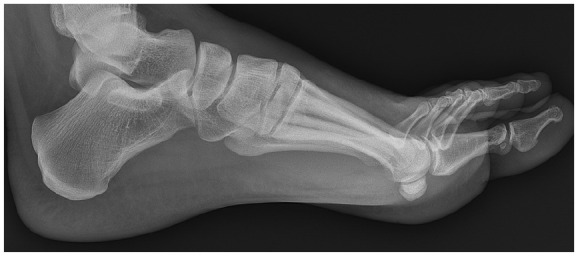

Methods: This study included patients who had a nondislocation Lisfranc injury with a proximal first webspace (between the medial cuneiform and second metatarsal base) diastasis of 2-5 mm, and underwent either a primary ORIF or primary arthrodesis. Preoperative weightbearing radiographs were reviewed to confirm subtle Lisfranc injuries. Of the 73 patients who met the inclusion criteria, 41 received a PA and 32 received an ORIF. Treatment selection was based on surgeon preference. Patient-reported outcomes via PROMIS scores were collected preoperatively and at least 2 years postoperatively. Subsequent procedures were also recorded.